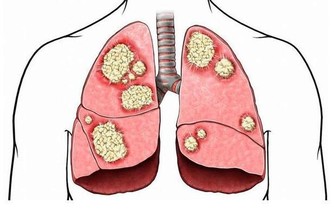

然而據英國《每日郵報》報道,許多牙膏的成分對我們的健康有害,

有些化學物質可能引起口腔癌、乳腺癌、神經疾病、心臟病、口腔潰瘍、牙齦損傷等疾病。